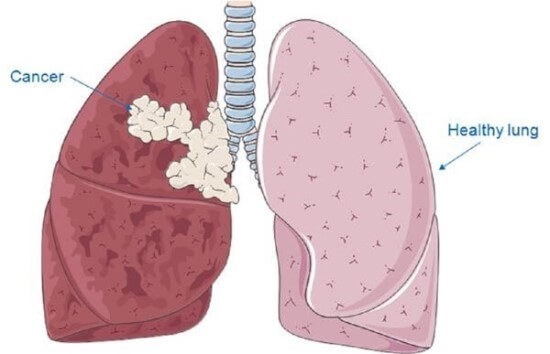

폐암 초기증상 : 폐암 4기 생존율은?

숨 쉬는 순간마다 위협하는 무서운 적, 폐암. 전체 암 사망 원인 1위를 차지하며, 진단 후 5년 내 사망률이 7~80%에 달하는 치명적인 질병입니다. 하지만 조기 발견 시 90%라는 놀라운 완치율을 기대